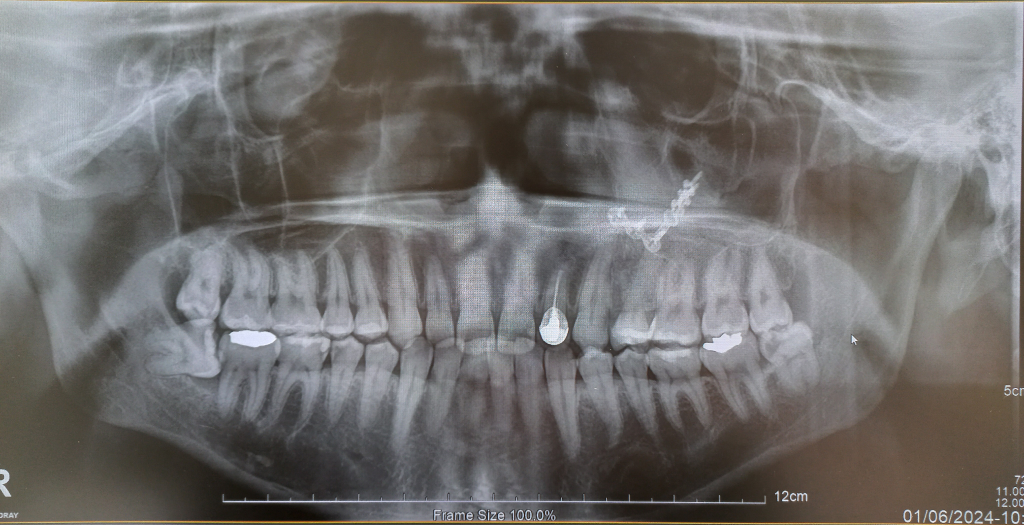

사이충치 인레이나 크라운 치료 한다는데 비용적절한가요?

2. 치식상 5,6번은 말씀하신 것처럼 우측하단이 맞습니다.

4. 주어진 파노라마 방사선 사진으로 봐서도 5번은 충치가 많이 진행되었고 6번도 어느정도 충치가 있는 것으로 보입니다.

전부다 비보험 진료이기 떄문에 치과마다 차이는 잇습니다. 평균적인 가격인거 같습니다. 치식은 가운데를 중심으로 4분악으로 나눠서 1-7번까지 표시를 하니 사진에서 보이는 5.6번은 우측 하악 5번 6번 치아를 말하는겁니다.